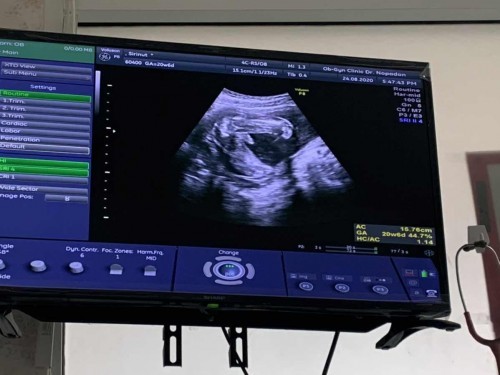

กว่าจะยอมให้ดู ปาเข้าไป21W ลูกชายสมใจอิแม่☺️☺️☺️